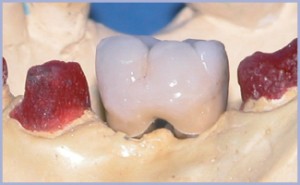

Dopo avere allestito il lembo a spessore totale (figg. 2, 3), si preparano due alveoli chirurgici, uno per l’impianto che sostituirà la radice mesiale, orientato in modo tale da risultare in asse con i carichi funzionali che si creano nella fase di entrata del ciclo masticatorio ed uno che sostituirà la radice distale, orientato in asse con i carichi funzionali che si creano nella fase di uscita. Poiché è necessario intaccare la corticale con estrema precisione, si inizia la preparazione con una fresa a palla montata su turbina (figg. 4, 5); si prosegue con il protocollo classico (figg. 6-14). Si inseriscono gli impianti, si assemblano i relativi tappi (figg. 15-19) e si sutura (fig. 20) secondo il protocollo bifase. Dopo tre mesi, quando l’osteointegrazione ha raggiunto una maturazione sufficiente ad assicurare la stabilità primaria degli impianti, si interviene con il secondo momento chirurgico per posizionare i tappi di guarigione e creare i condotti mucosi (figg. 21-24) che si epitelizzeranno in circa dieci giorni. Segue la presa delle impronte mediante transfer da impronta (figg. 25-28). Il tecnico assembla gli analoghi da gesso sui transfer, sviluppa i modelli, monta i monconi sugli analoghi ed esegue il fresaggio (fig. 29). In studio si verificano i monconi (fig. 30) e si rimandano in laboratorio per la preparazione delle cappette (fig. 31) e la relativa ceramizzazione (fig. 32).

- Fig. 29

- Fig. 30

- Fig. 31

- Fig. 32